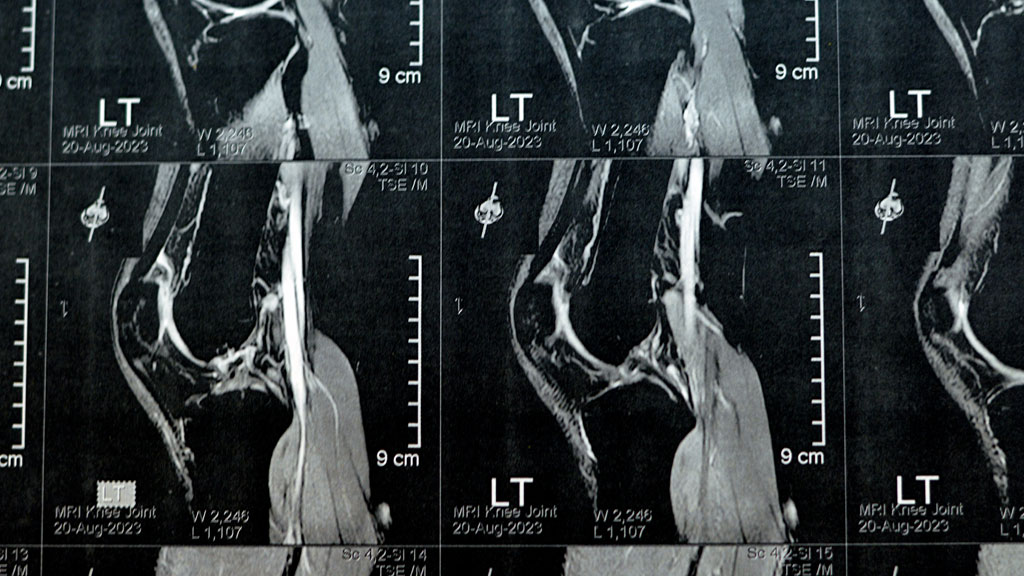

J+7 à J+21 : IRM et consultation spécialisée

L’IRM révèle l’étendue des dégâts. Et c’est souvent là que les patients découvrent une réalité que les articles en ligne passent sous silence : vous n’avez probablement pas que le LCA de touché. J’y reviendrai plus bas, mais sachez que la majorité des ruptures s’accompagnent de lésions associées.

Muni de vos images, vous consultez un chirurgien orthopédiste spécialisé dans le genou. Pour comprendre en profondeur les mécanismes de la rupture du ligament croisé, cette consultation est déterminante. Le spécialiste analyse vos images, évalue votre stabilité résiduelle, et surtout : il vous pose des questions sur votre mode de vie.